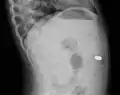

- AP X ray showing a 9mm battery in the intestines

- Lateral X ray showing a 9mm battery in the intestines